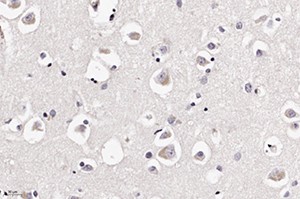

В периваскулярных астроцитах и ганглиозных клетках определялись аналогичные внутриядерные вакуоли с базофильными включениями (см. рис 2 и рис. 3).

При ИГХ обнаружено наличие антигена вируса в клетках нейронов и астроцитов (см. рис. 5 и рис. 6). В то же время реакция к S-гликопротеину вируса SARS-CoV-2 поверхностных рецепторов была отрицательной.